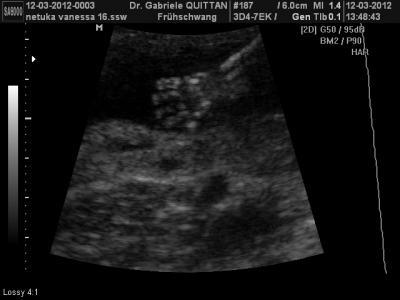

mal was von unserem buben :-)